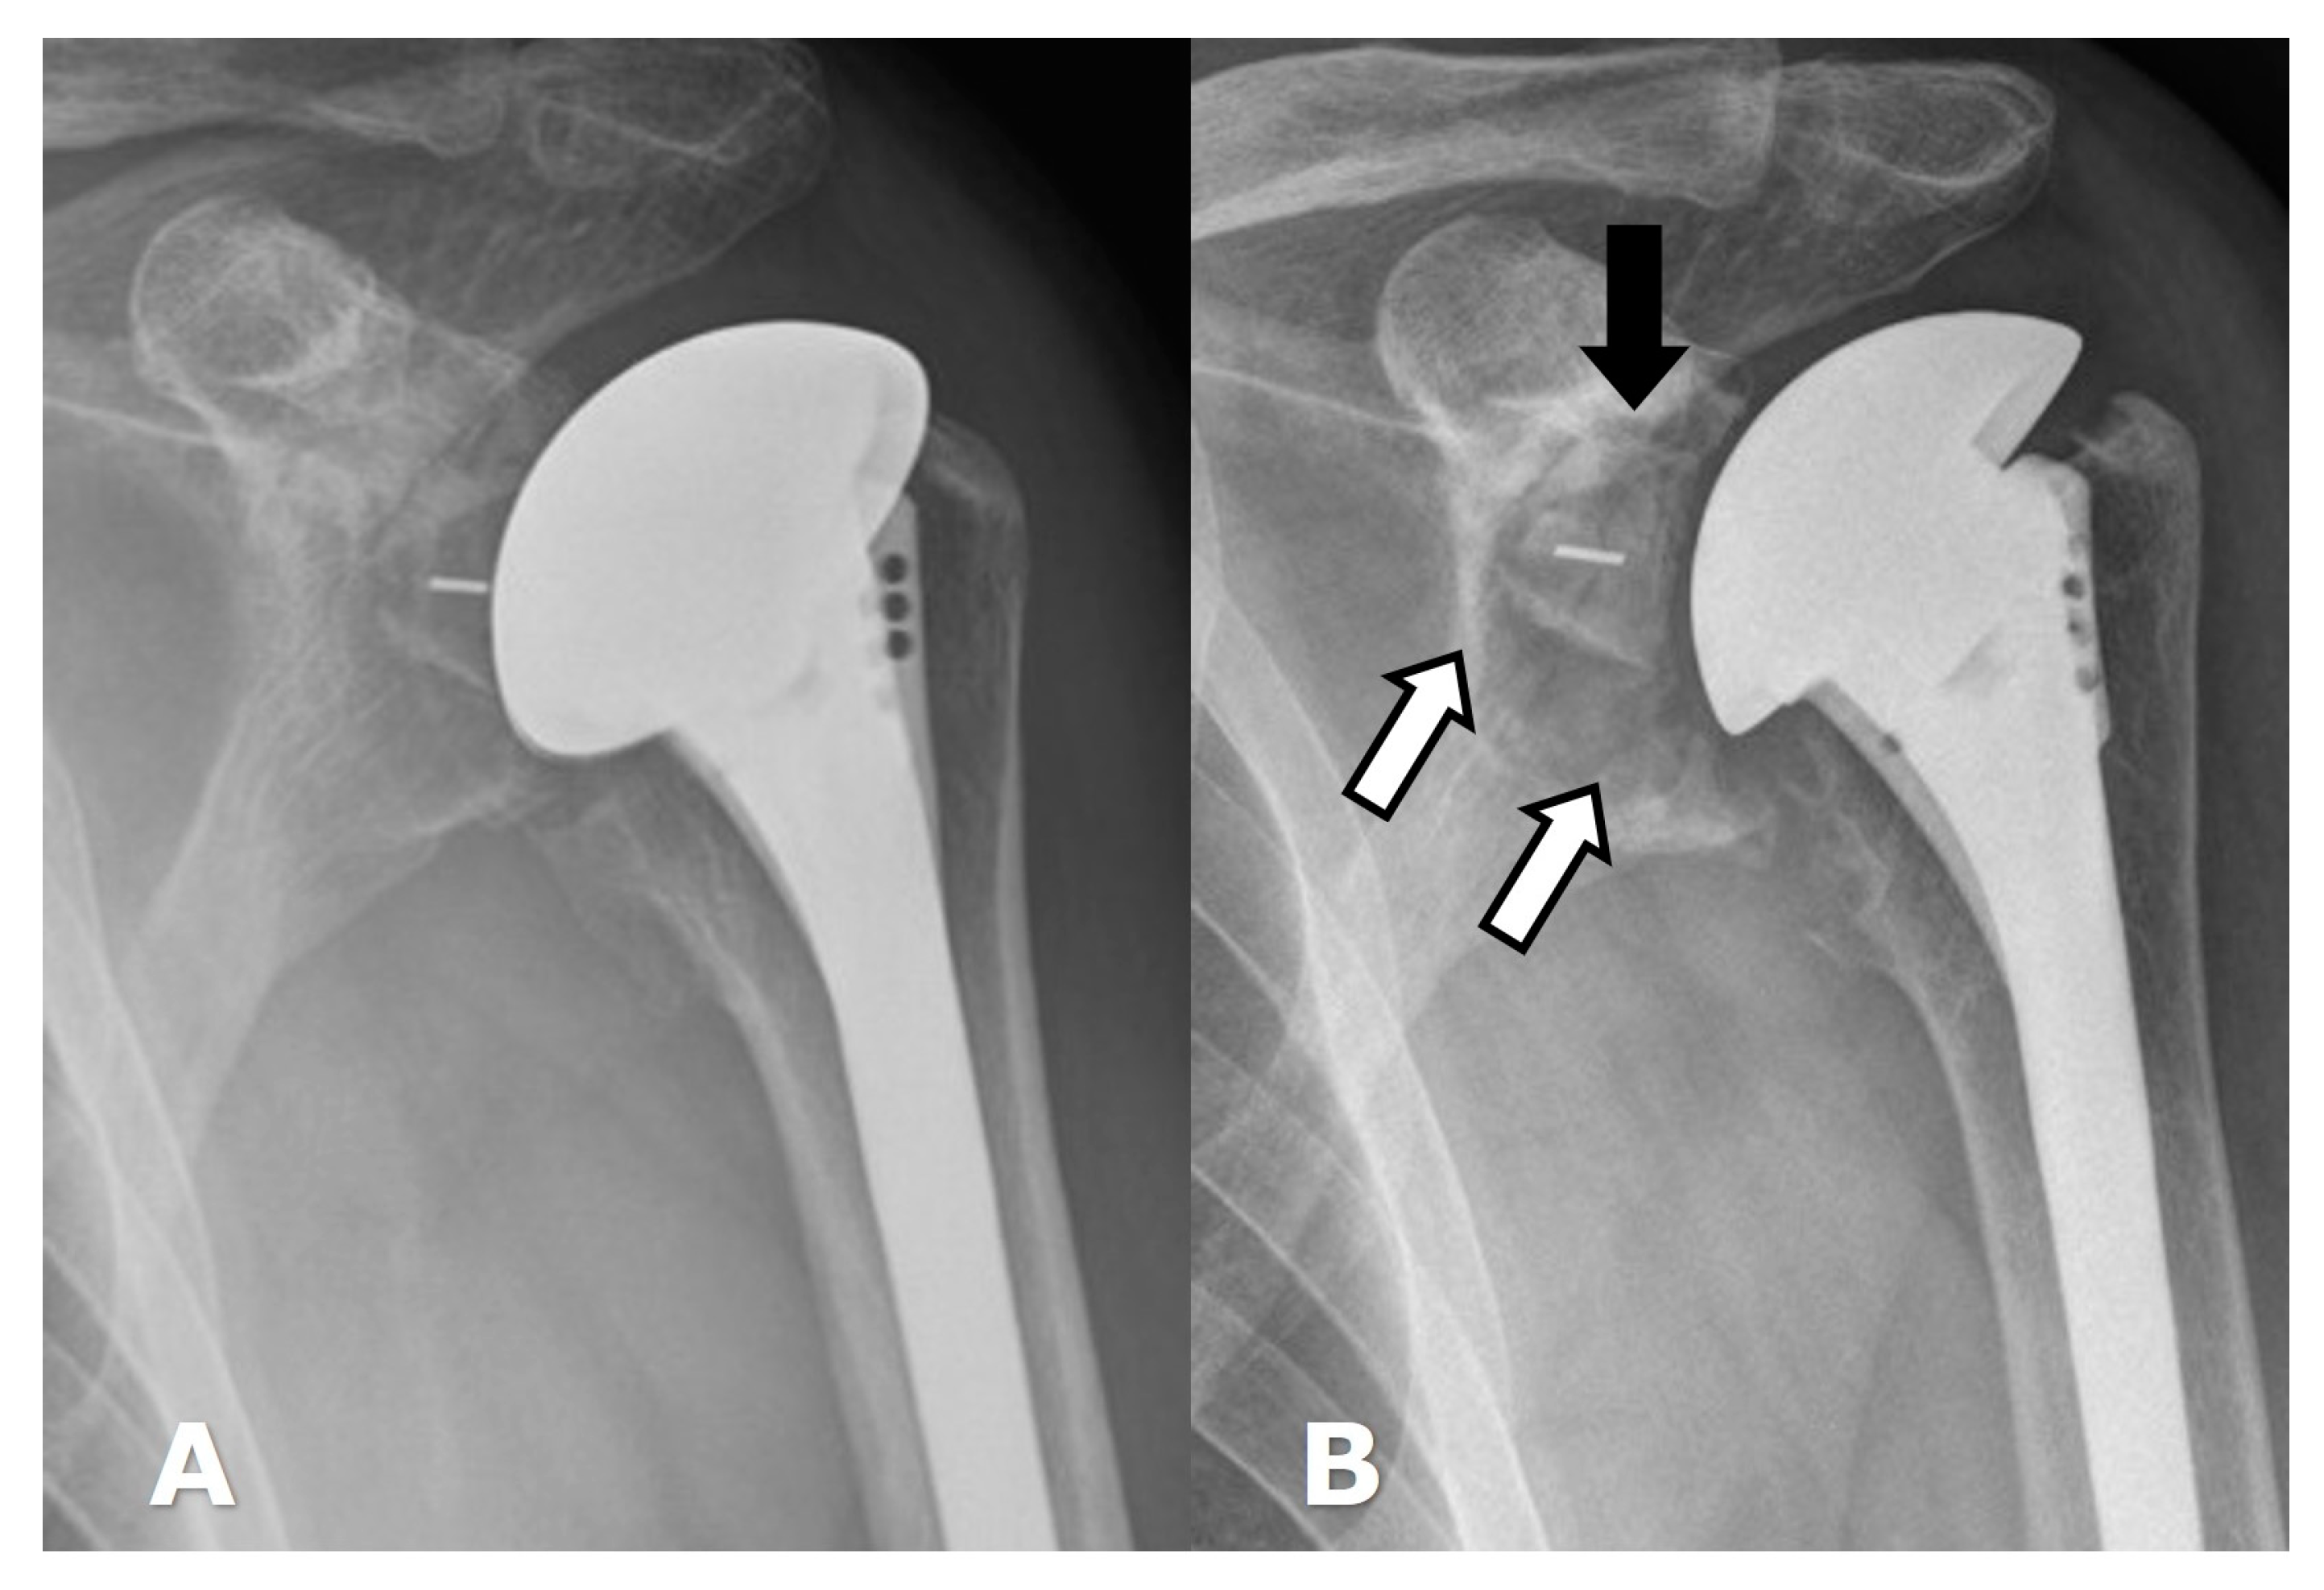

5.1.2. Hemiarthroplasty (HA)